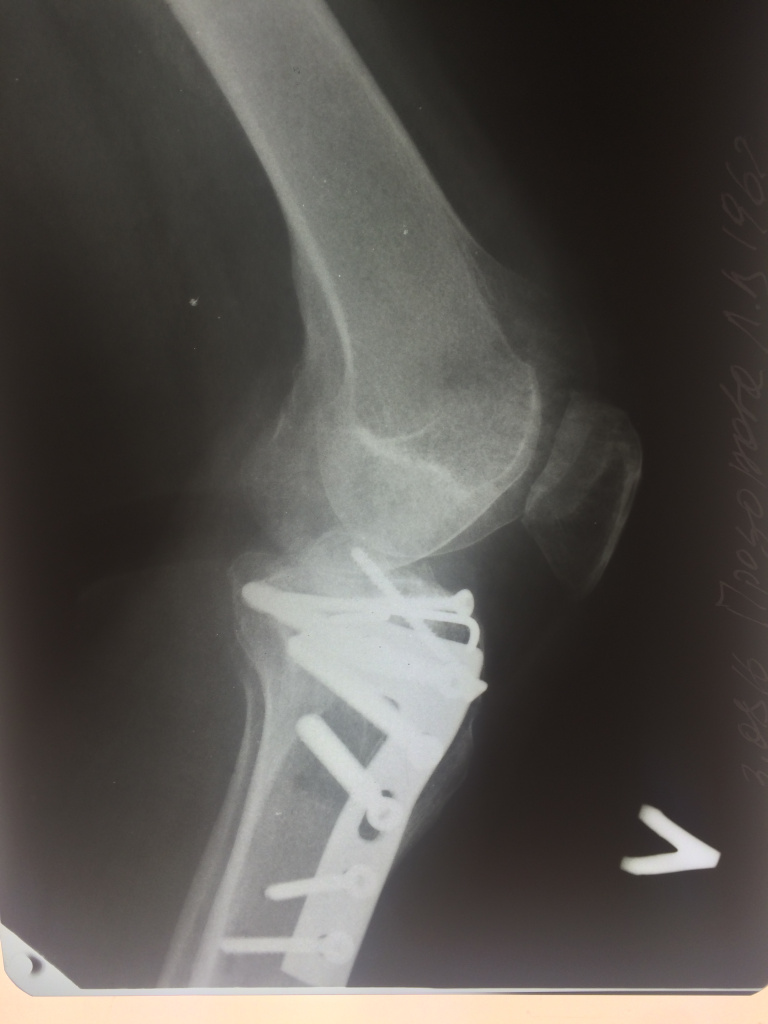

Использование материала Остеоматрикс при импрессионном оскольчатом переломе наружного мыщелка большеберцовой кости по типу Schatzker II

Использование материала Остеоматрикс при импрессионном оскольчатом переломе наружного мыщелка большеберцовой кости по типу Schatzker II.

Операция - открытая репозиция, остеосинтез большеберцовой кости опорной пластиной с костной ксенопластикой маетриалом "Остеоматрикс". На контрольных снимках в три и шесть месяцев имеется консолидация перелома, миграции фиксатора нет, имеется остеоинтеграция ксенопластического материала. Функция коленного сустава полная.